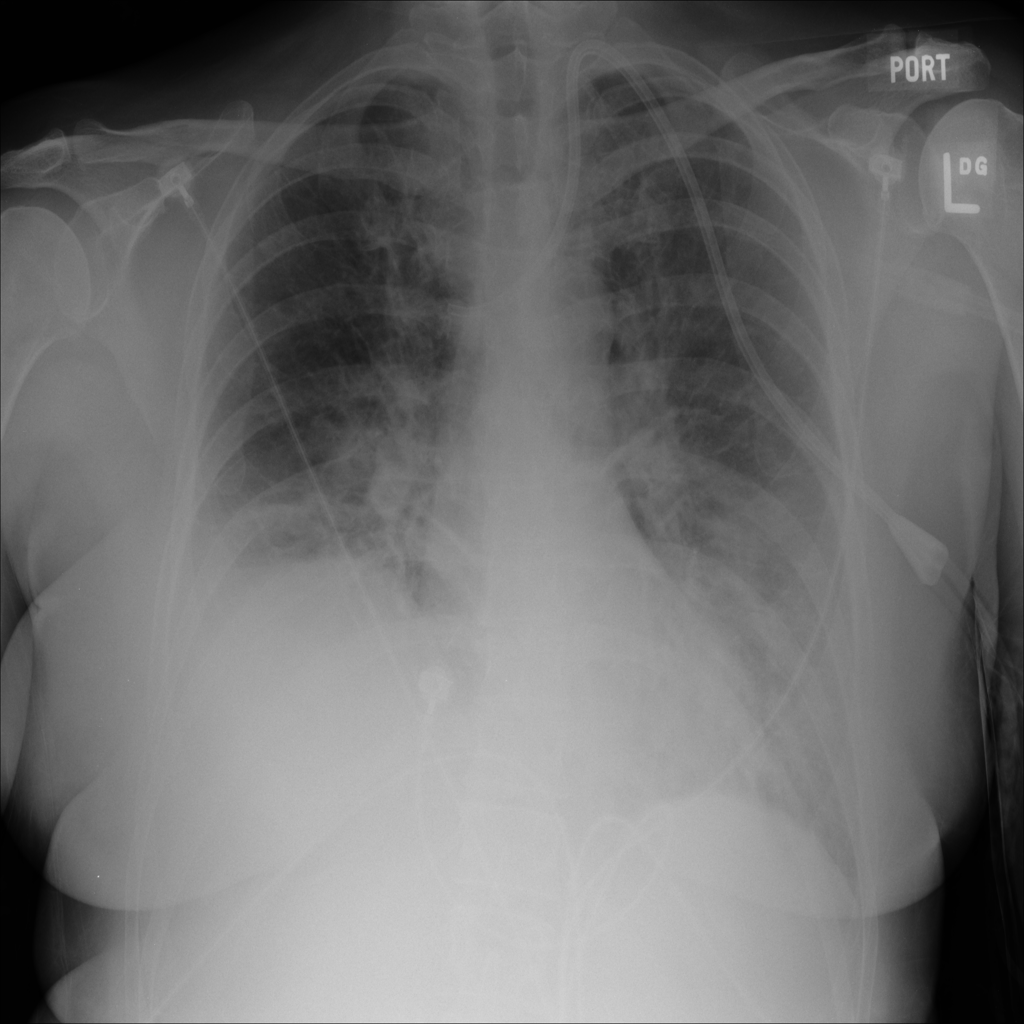

PAT-E828 · IMG-004Edema

PAT-E828 · IMG-004

AP